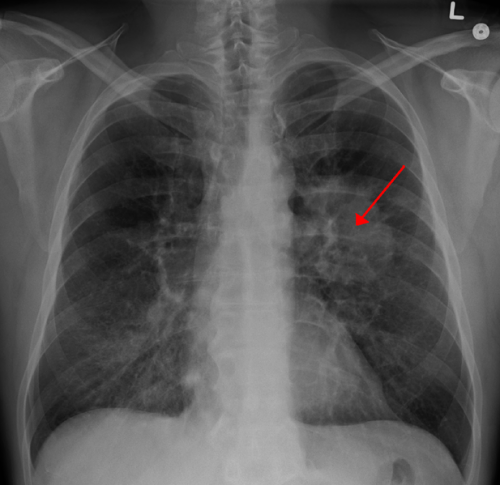

Lung CA seen on CXR. Credit: James Heilman, MD/Wikipedia

The most common type of lung cancer, non-small cell lung cancer (NSCLC), continues to be difficult to treat, with five year survival rates of about 36 percent for stage 3A tumors. Jefferson College of Pharmacy researchers are developing a new treatment approach based on nanotechnology that was recently shown to be effective in mouse models of the disease. The research was published in the journal Molecular Pharmaceutics.